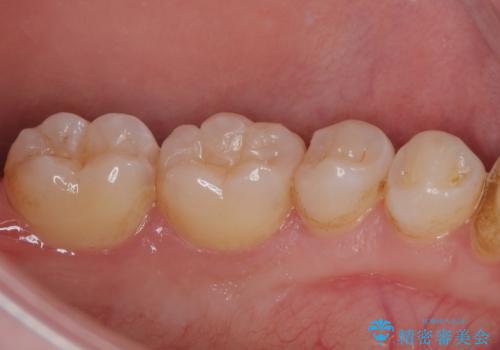

精密な型取りと、ラバーダム防湿下での接着操作により、歯と詰め物の隙間を最小限にとどめることができ、処置後はしみる症状が一切なくなりました。